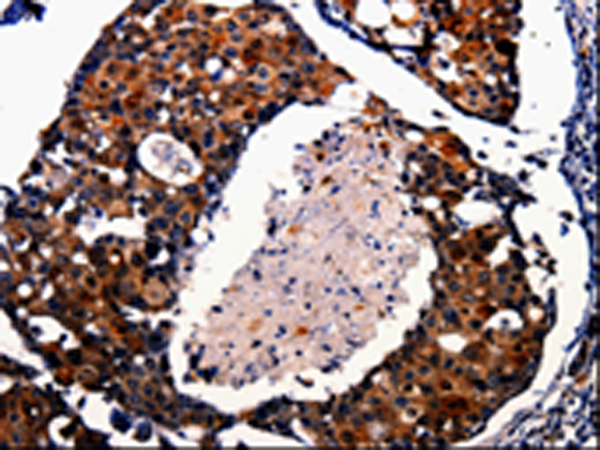

分类: 科研抗体货号: P00095别名: DWFC; JV5-1; MADH5应用: WB,IHC反应种属: Human, Mouse, Rat